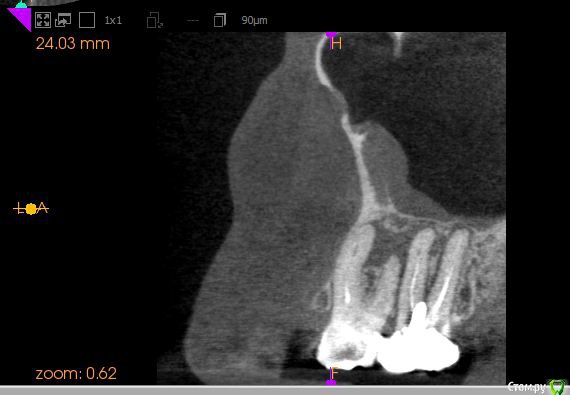

Диана135 Опубликовано 31 марта, 2017 Поделиться Опубликовано 31 марта, 2017 Здравствуйте! Год назад лечила зубы, осенью над одним из них появился флюс, который до сих пор не исчезает, это доставляет мне дискомфорт. Стоит ли продолжать лечение или проще удалить? Прилагаю описание КЛКТ: Зуб 2.6 коронковая часть восстановлена рентгеноконтрастным материалом. Трех корневой, четырёх канальный (в медиально-щечном 2 канала). В медиально-щечном корне каналы прослеживаются, в одном из каналов, в верхней трети определяются фрагменты рентгеноконтрастного материала. В небном корне в верхней трети рентгеноконтрастный материал. В средней трети корня определяется внутрикорневой очаг деструкции 2,2×3,7 мм с резорбцией дистального края и линией просветления от очага деструкции в медиальную сторону апикальной трети. В проекции медиально- и дистально-щечных корней определяется ограниченный очаг деструкции однородной структуры, с неровными контурами, с разрушением наружной кортикальной пластинки и распространением процесса в сторону корней 2.8 зуба. Кортикальная пластинка дна верхнечелюстного синуса в проекции деструкции истончена с набуханием слизистой до 4 мм.Зуб 2.7 Коронковая часть восстановлена рентгеноконтрастным материалом. Трех корневой, четырёх канальный (в медиально-щечном 2 канала). В каналах определяется рентгеноконтрастный пломбировочный материал: в медиально-щечном корне, один из каналов не обтурирован, другой не до верхушки, в дистально-щечном обтурация не до верхушки, в небном до апикального отверстия. В области верхушек медиально и дистально щечных корней определяется деструкция до средней трети длины корней, с расширением пространства периодонтальной связки.Отмечается общая горизонтальная убыль костной ткани до 3 мм. Ссылка на комментарий

Диана135 Опубликовано 1 апреля, 2017 Автор Поделиться Опубликовано 1 апреля, 2017 Скриншоты снимка. Ссылка на комментарий